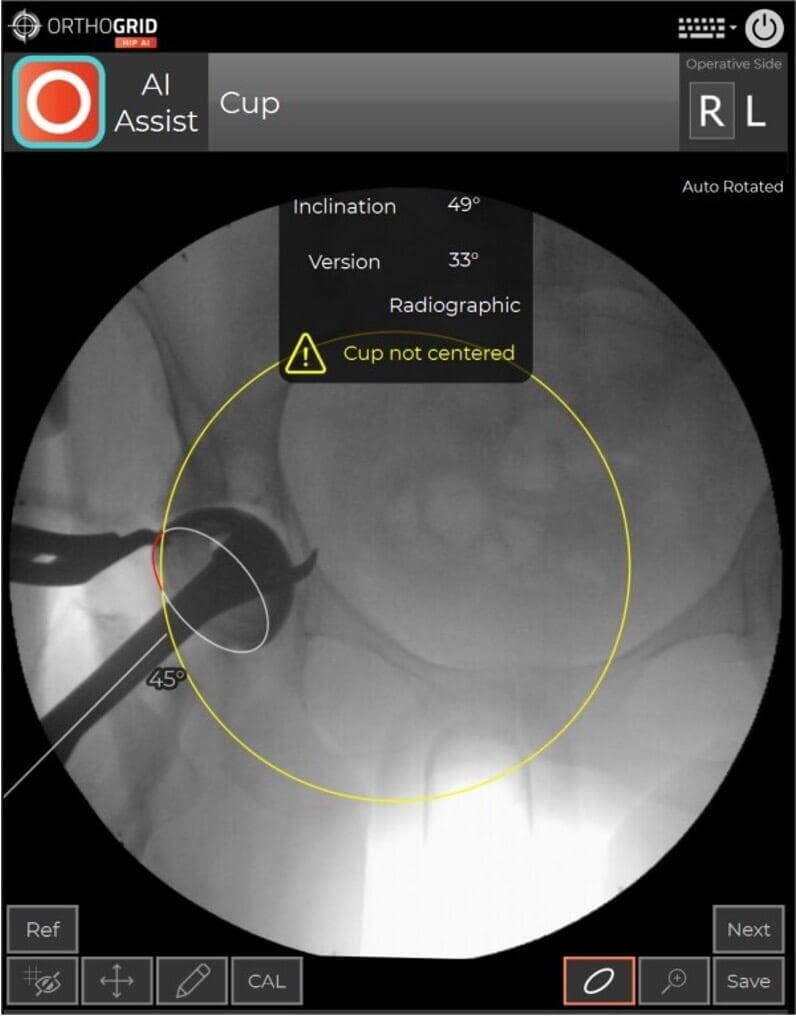

- If your cup is not in the center of the image, the cup measurement can be influenced by parallax. You'll see the Hip AI warning message. Retake image and center the Cup while keeping both Teardrops in view to Keep the Pelvis Tracking